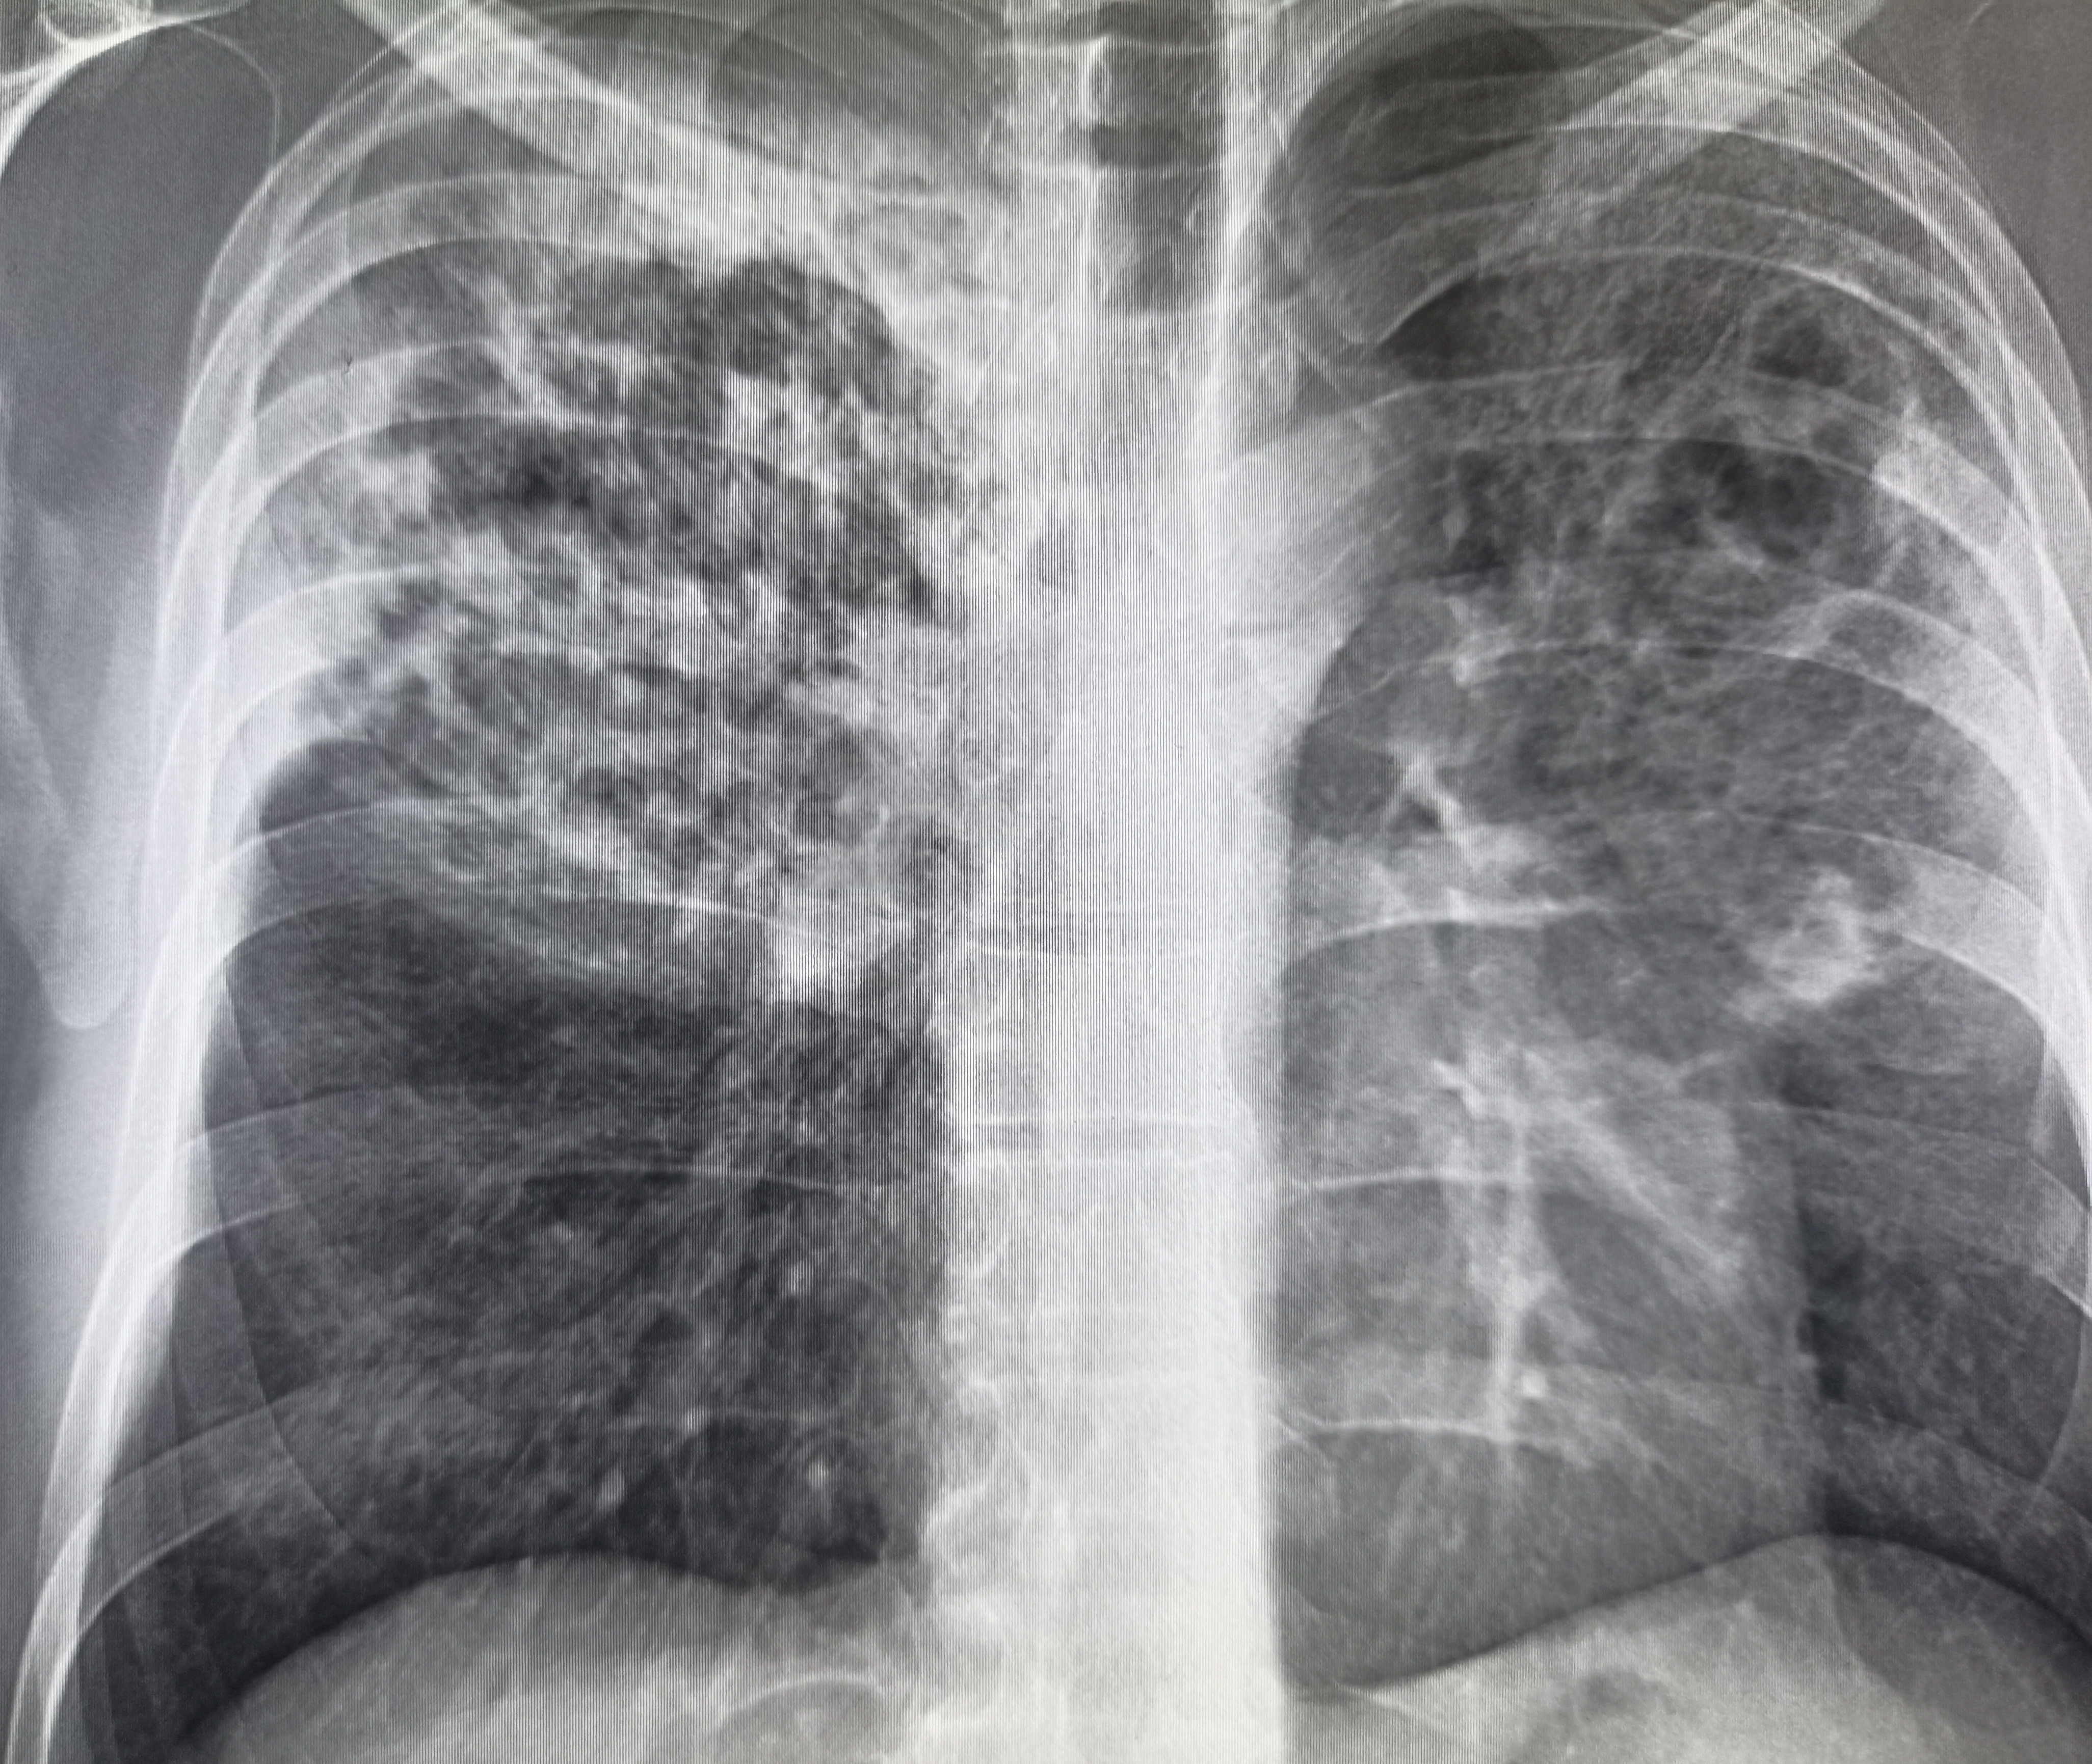

IMG20251008114159.jpg

Чо тут у нас?

>>325599559

Типичный рак легких

Аноним 16/10/25 Чтв 08:58:28 #14 №325599625

Где пиздецома?

вообще, как клинический диагноз. я бы предположил тубик, тут и затемнения есть и в корнях кругленькие л/у? и какая то диссеминация справа.

Там он был, это пост туб изменения снята с учета.